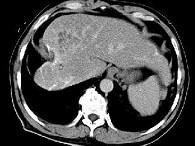

问题 女性,56岁,腹胀、双下肢浮肿、乏力、食欲不振,影像所见如下图,最佳的诊断是()

选项 A.酒精性肝硬化并肝血管瘤 B.血吸虫肝硬化并肝癌 C.肝炎后肝硬化并肝癌 D.局限性脂肪肝 E.原发性肝癌

答案 B